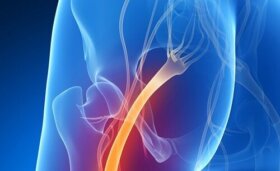

이 기사에서는 요통의 원인 및 치료 방법에 관해 살펴볼 것이다. 서울대학교병원 웹사이트의 건강정보에 따르면, 요통은 허리에 갑작스럽게 통증이 발생하는 현상으로…

쉽게 진단이 되는 건강 문제들이 있다. 하지만 좌골 신경통처럼 다른 문제들과 증상을 착각할 수 있는 질병들도 있다. 계속 읽어가면서 좌골 신경통이 있는지…